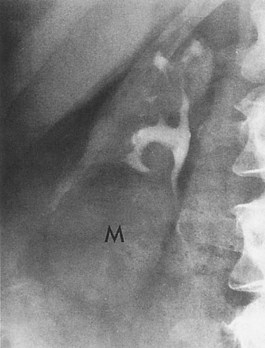

The diagnosis is established radiographically. Tissue gas that is distributed in the parenchyma may appear on abdominal radiographs as mottled gas shadows over the involved kidney (Fig. 10–22). This finding is often mistaken for bowel gas. A crescentic collection of gas over the upper pole of the kidney is more distinctive. As the infection progresses, gas extends to the perinephric space and retroperitoneum. This distribution of gas should not be confused with cases of emphysematous pyelitis in which air is in the collecting system of the kidney. Emphysematous pyelitis is secondary to a gas-forming bacterial UTI, often occurs in nondiabetic patients, is less serious, and usually responds to antimicrobial therapy.

Figure 10–22 Emphysematous pyelonephritis; plain film. Extensive perinephric (long arrows) and intraparenchymal (short arrows) gas secondary to acute bacterial pyelonephritis.

(From Schaeffer AJ. Urinary tract infections. In: Gillenwater JY et al, editors. Adult and pediatric urology. Philadelphia: Lippincott William & Wilkins; 2002. p. 211–72.)